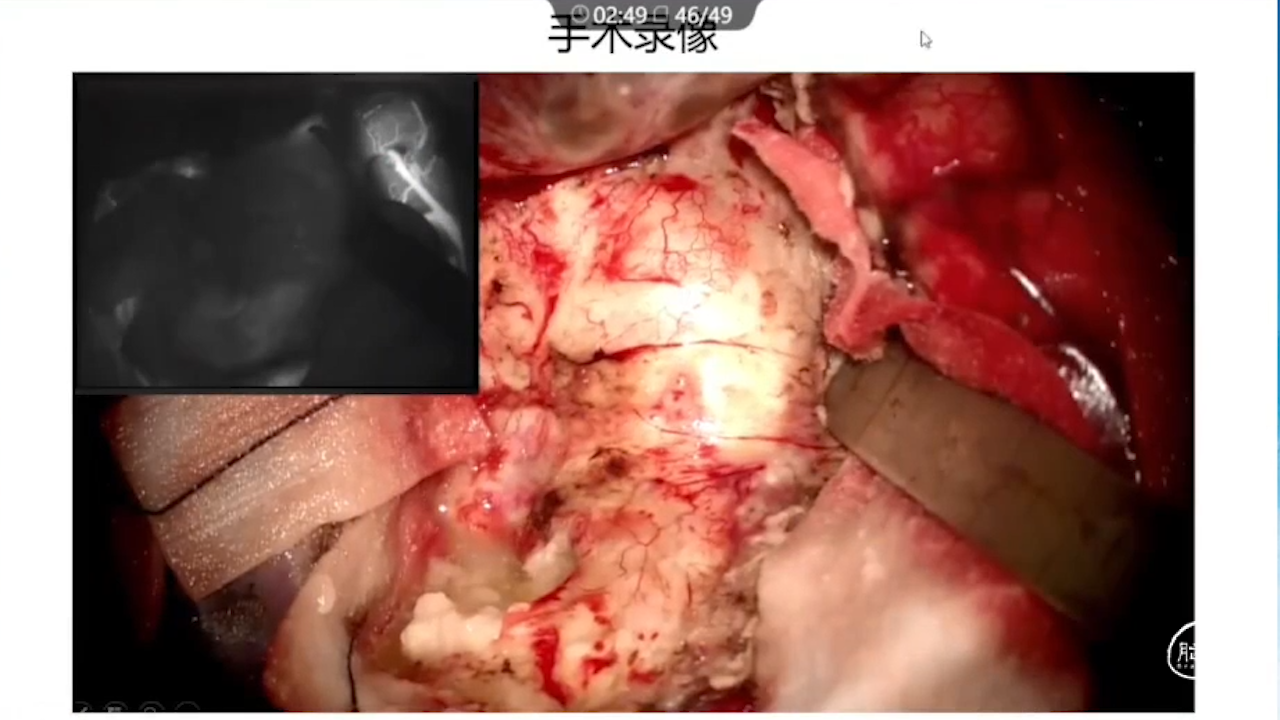

2、术中硬膜剪开及肿瘤切除时逐步接近功能区,在剪开硬膜前,可行B超定位桥静脉以防误伤,根据桥静脉的位置灵活调整硬膜的剪开方向。

3、在显微镜下用弹簧剪松解桥静脉的蛛网膜束带,使其尽量长的游离。

4、采用较窄的脑压板轻柔牵拉皮层,减少桥静脉的牵拉张力,同时加强湿化,明胶脑棉保护。

5、减少术中误伤静脉和减少过分用双极电凝烧灼静脉,若有撕裂出血,则不宜电凝,防止静脉血栓形成,取小块明胶海绵点对点脑棉压迫即可成功止血。

7、术中辅助技术:实时定位并保护静脉,监测其通畅性(荧光造影、Flow800)。